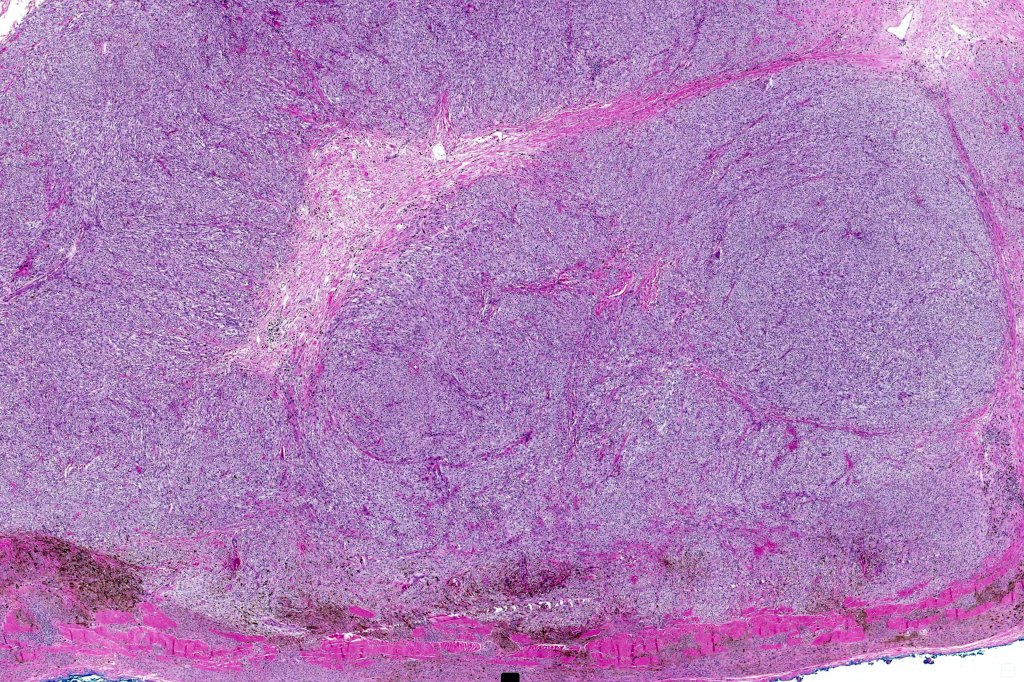

Histological features

•The latter may show a dumbbell appearance at low power or scanning magnification

•Develops within a precursor lesion as one or more nodules of epithelioid or spindled cell melanoma

•Or melanoma showing admixed blue nevus-like features (dendritic cells and melanophages) in the absence of a precursor lesion